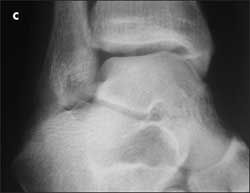

(Answer on next page.)Right ankle pain after a basketball injury: The frontal view of the ankle reveals soft tissue swelling that is predominantly lateral (A, yellow arrow). A small ossific fragment is evident distal to the lateral malleolus (A, white arrow); close inspection shows this to be well-corticated. The remainder of the osseous structures are intact. The lateral view reveals a joint effusion in the talotibial joint (B, arrow); no fractures are visible. In the oblique view (C), the osseous structures appear intact.

The well-corticated ossific fragment is consistent with an old injury, but it is in the region that is now extremely tender. The joint effusion indicates that the current injury is severe. However, this is a nonspecific finding; joint effusions are seen with fractures and ligament and tendon injuries.